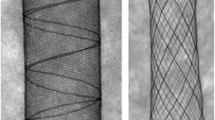

A better understanding of the cellular effects of stent design on blood and vessel reactions can potentially contribute to both product design development and procedural planning [5, 6]. State-of-the-art implants can be divided into two groups with regard to manufacturing and design features: laser-cut stents (LCS) and braided stents (BS). LCS involves removing material from a tube, creating openings surrounded by struts that deform from the radially compressed configuration to the expanded configuration. In contrast, BS comprises multiple wires interwoven into a cylindrical shape. The design of BS reduces deformation of the wire by allowing relative sliding between wires. The divergent manufacturing processes result in consistent differences between both stent technologies, particularly regarding stent elements (squared struts in LCS vs. round wires in BS), stent profile (thicker in BS because of crossing wires at interconnecting points), and radial expansion force (high in both stents, depending on construction parameters and size) Moreover, surface finishing is usually different in the two technologies [7].

Both the LCS (Acclinoflex®/Credo®) and BS (Accero®) used in this study are clinically available (Acandis GmbH Pforzheim, Germany) and compare the superelastic nickel titanium alloy Nitinol©. LCS have six openings around the circumference and a wall thickness of 50 µm. The struts have an alternating width of 40 and 32 µm, resulting in an asymmetrical structure for improved flexibility. Three radiopaque markers are placed at each end. For this study, LCS with a diameter of 4.5 mm and lengths of 15 mm or 20 mm were used.

The BS used have a diameter of 2.5 mm or 4.5 mm. The stent comprised a 50 µm single wire bent at each end in multiple loops, resulting in six and nine openings around the circumference for both sizes, respectively. Implant thickness at the wire crossing points was 100 µm. The open wire ends were connected with a radiopaque marker in the middle of the stent.

Representative histological images of a transverse section of a laser-cut stent (LCS; a) and a braided stent (BS; b) in the subclavian artery at 3 days and 28 days follow-up (c, d). An asterisk shows thrombus formation. White arrows show compression of elastic fibres in the tunica media. Representative histological images of a transverse section of an LCS (e) and a BS (f) in the subclavian artery at 28 days follow-up showing intimal hyperplasia. # shows the neointima